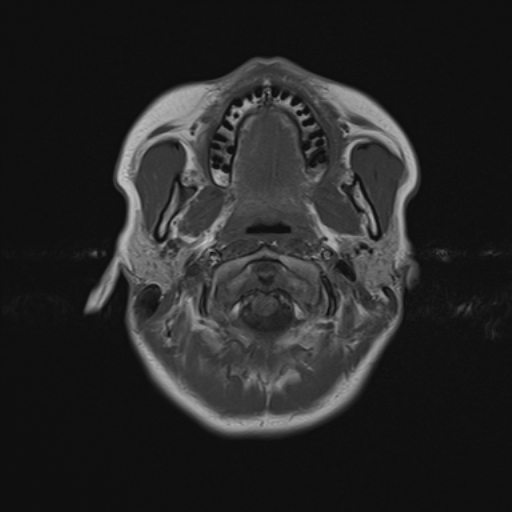

Nome Paziente: MACARI^NATALIA Identificativo: VSM_01222260 Data di Nascita: 07-06-1995 Sesso: F

Esame: RM ENCEFALO MDC del 24-03-2026